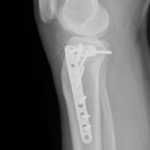

- Wrist Fractures.

if the fracture is displaced, surgery may be needed to put the bone back into the correct position and fix the bone with Plates & screws or nails for adequate healing to occur.